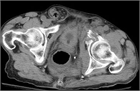

1. 鼠径部ヘルニアの分類がわが国独自の日本ヘルニア学会(JHS)分類から国際分類(EHS classification)に統一された。

1. わが国のすべての鼠径部ヘルニア患者において、日本ヘルニア学会の鼠径部ヘルニアの分類(令和3年改訂版)は、術式選択の基準や術後成績の客観的な比較のために有用である(推奨度2)